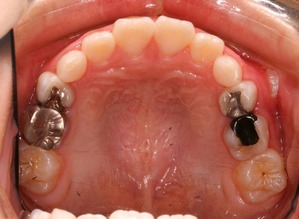

横から生えてきた永久歯も向きは悪いですが、かなり良い方向に降りてきました。

一方で出てきたときの状況は

現在の状況です

中学2年生になりました。

上顎も下顎もそこそこの歯列になっていると思います。

咬み合わせも良好です

なんと、大人の歯は虫歯0本で管理されてます!

こういった部分は歯列矯正の技術的な部分はまったくなく、知識という部分をふんだんに応用した結果です。